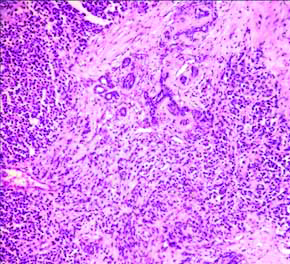

Microscopy showed breast parenchyma with a neoplasm arranged in sheets, lobules, nests and alveolar pattern [Table/Fig-2,3]. The tumour cells are small round with scant cytoplasm, round vesicular nucleus separated by fibrous septa seen infiltrating into the adjacent fatty tissue [Table/Fig-2,3]. Stroma showed lymphocytic infiltrate. The NAC, superior, inferior margin showed tumour infiltration. Rest of the margins and posterior margin were free. Five out of 11 nodes showed metastatic deposits with similar morphology [Table/Fig-4]. With this histology, we came to the conclusion of possibilities of small round cell tumour of breast.

Breast parenchyma with a neoplasm composed of loosely cohesive cells (H&E, 10x view).